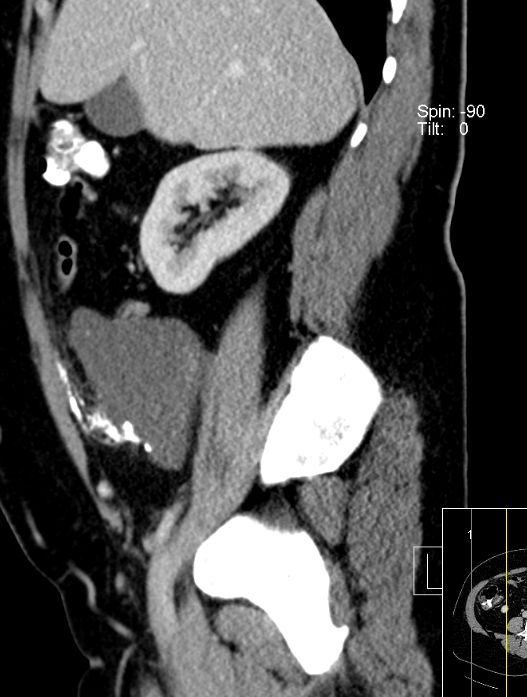

| Fall 1 | 51-jährige Frau mit primärem Peritonealkarzinom. | |||

| Therapie: Partielle Peritonektomie, HE mit Adnexen, Sigmaresektion (Hartmann), Omentumresektion. | Histologisch: Gut differenziertes seröses Adenokarzinom mit massenhaft Psammomkörperchen (Psammokarzinom). G1.Staging: pT3c. | |||

6 Monate später Lebermetastasen.![]() |